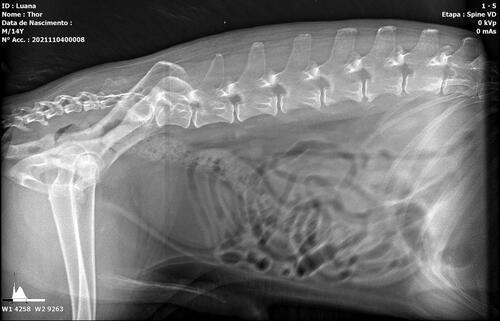

Thor é um senhorzinho que sofre com a síndrome da cauda equina, que é uma doença grave causada pela compressão e inflamação do feixe de nervos na parte inferior do canal vertebral. A gravidade se dá ao fato de poder resultar em paralisia, incontinência intestinal / urinária e a outros problemas de sensibilidade e perda de movimento.

Thor já apresenta todos os sintomas e precisa passar por procedimentos veterinários, necessita de fisioterapia para estimular o retorno do controle esfincteriano (válvula urinária e fecal) e medicações. Uma cirurgia também pode ser o caminho de acordo com o neurologista veterinário.